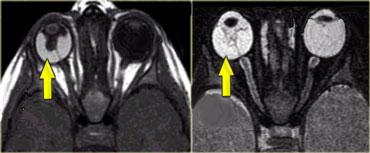

Khoang nội nón được đánh dấu bằng các mũi tên và nằm bên trong hình nón cơ. Khoang này chứa thần kinh thị giác, các mạch máu và các dây thần kinh sọ III, IV và VI.

Bên trái là hình ảnh của một bệnh nhân bị giãn tĩnh mạch hốc mắt, người này nhận thấy mắt trái bị lồi ra khi rặn.

Hình trên là lúc nghỉ ngơi và hình dưới là trong nghiệm pháp Valsalva tại thời điểm hắt hơi.

Trong nghiệm pháp Valsalva, tĩnh mạch giãn giãn nở cực độ (mũi tên đỏ).

Lưu ý rằng trong nghiệm pháp Valsalva, tĩnh mạch mắt trên ở bên bình thường cũng giãn ra (mũi tên xanh).Kết luận